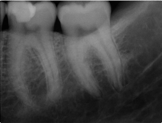

Treatment Examples

Conventional Treatment with Standard Core Restoration

Non-surgical endodontic treatment with resin core build up

Conventional endodontic treatment with alloy core build up

Conventional Endodontic Treatment with Post and Core Coronal Restoration

Conventional Endodontic Treatment/Retreatment with Prefabricated Bonded Post and Core

Conventional Endodontic Treatment with Minimal Clinical Crown: Cast Post and Core Coronal Restoration

Surgical Endodontic Treatment

Hemisection with Cast Post and Core

Surgical Exposure of ECIR with External Cervical Root Repair, Conventional RCT with Prefab Post

MB Root Amputation

Long Term CaOH Cases

12 Month CaOH Treatment

14 Months CaOH Treatment

All Treatment performed by Dr. Brian A. Christopherson